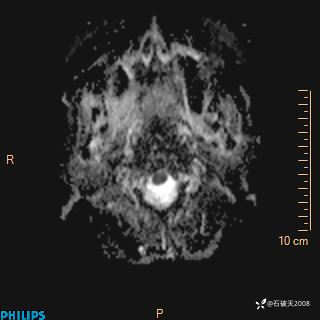

DWI

ADC